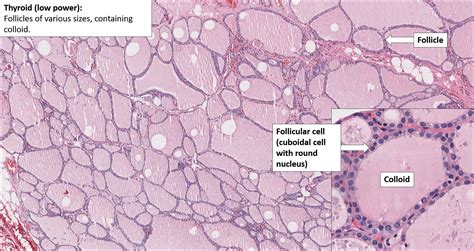

Understanding the Thyroid Gland

The thyroid gland is a vital part of the endocrine system, responsible for producing hormones that regulate metabolism, heart rate, body temperature, and more. These hormones, primarily triiodothyronine (T3) and thyroxine (T4), are essential for the body’s overall functioning. The thyroid gland is controlled by the pituitary gland, which releases thyroid-stimulating hormone (TSH) to regulate thyroid hormone production.